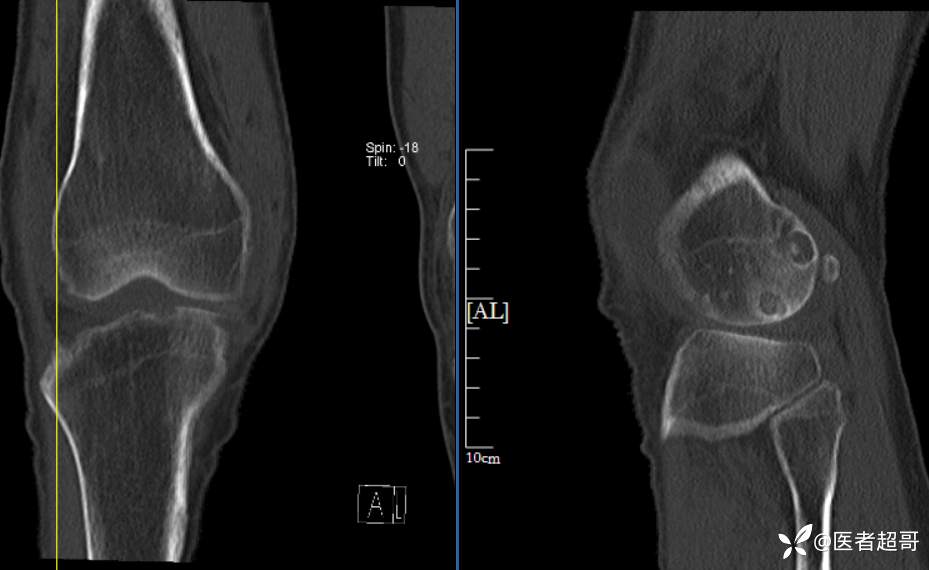

华夏览雄 等 2 位达人已点赞男性,55岁,右膝关节疼痛伴活动困难2年余

两年前外院行右膝包块切除术,术后病理为“肉芽肿”,具体不详,患者术后经常右膝关节积液,右膝活动困难,右膝疼痛明显

实验室检查:白细胞计数:9.0×10^9/L;葡萄糖(空腹):6.93mmol/L↑